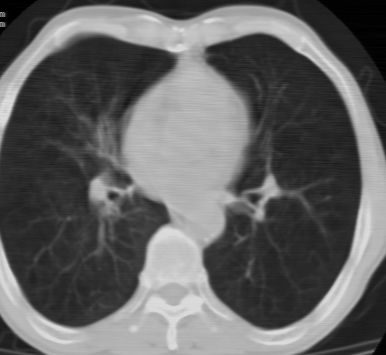

标题: CT24783:m71,既往肺心病史3年,现咳嗽,憋喘。 [打印本页]

标题: CT24783:m71,既往肺心病史3年,现咳嗽,憋喘。

2、全小叶性肺气肿。

1)左肺上叶周围型肺癌可能。2)两肺全小叶型肺气肿。